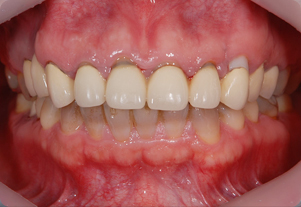

ジルコニアクラウン

金属と同じ強度を持ち、生体親和性の高い

安全かつ美しさを兼ね備えた素材です。

人工ダイアモンドと呼ばれるジルコニアは、金属を使用していないため金属アレルギーをお持ちの方でも安心してご使用いただけます。従来の金属に比べ約1/3の軽さで自然な噛み心地を体感していただけます。

Before

After